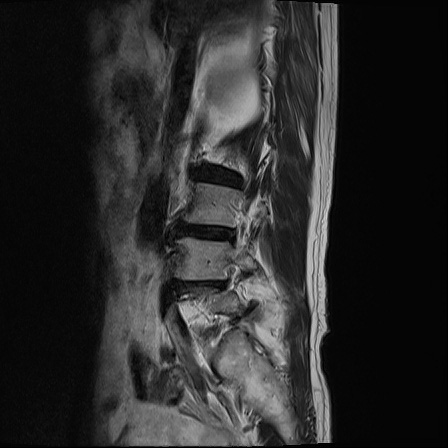

Ӵϲ ɿ ô ô 㸮 ٸ ̾ϴ. ϵ Ͻð ܻ 㸮 20⵿ ͽϴ. mri ˻ ɿ Ȳ ʹ ؼ Ȳ̶ ߽ϴ. ϻȰ ϰ 鼭 ½ϴ. ̴ ø鼭 Ͻô Ȳ ̷ ġ ص ȸ ϴ. δ Ҵµ, ù ȸԲ ˷ֽ ϰ β ϰ, ˷ֽ ü ƮĪ ϸ鼭 ȭǸ鼭 Ӵϲ ȸų ְ ǰ, β 鼭 ʴ β ؾϴ ŷο 1ϸ ijħ ڸ ǥ Ʈ ߽ϴ. ȸ ȭϽø鼭 Ϸ簡 ٸ ȸǽð 4ְ Ǿ Ǯ鼭 ¦ ҽϴ. ħ ȸ ȭϸ鼭 ڼ ü ƮĪ ϴ. ȥڼ Ͻʴϴ. ٳø鼭 ó Ͻ ʴϴ. ̾ ְ ̳ ߵ ʰ ϴ ȸԲ Ͻʴϴ. ʹ ϸ鼭 ϴ. Ȩ - ϱ ٴ Ȳ MRIԴϴ. |